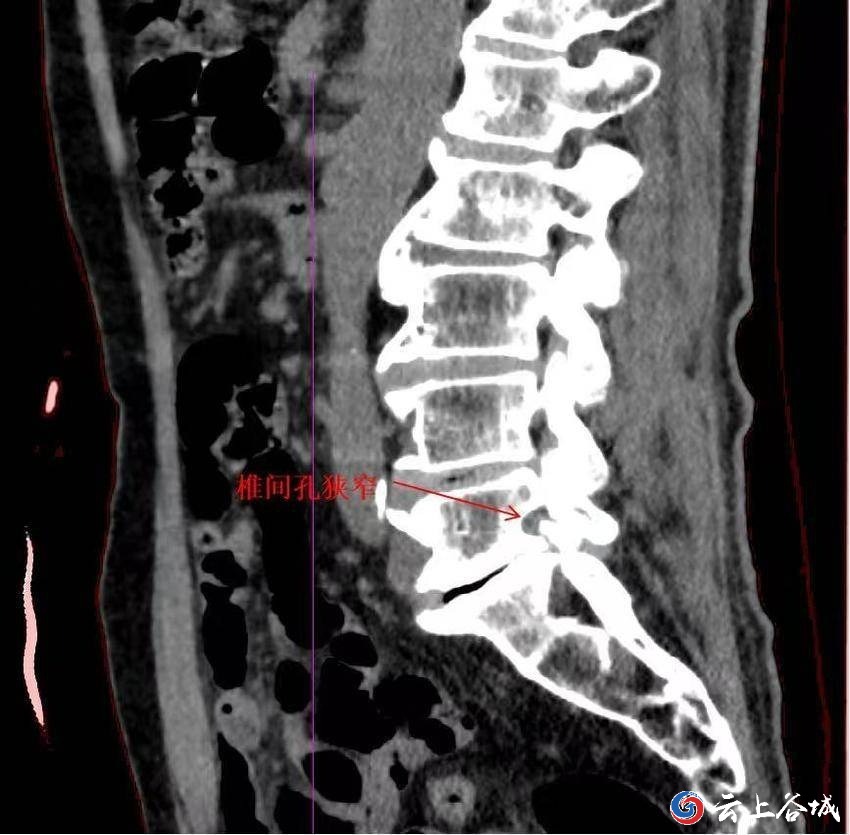

CT提示1:检查发现侧隐窝狭窄、小关节增生等。